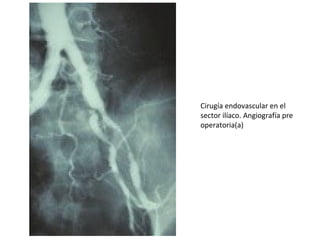

Cirugía endovascular en el

sector ilíaco. Angiografía pre

operatoria(a)

Realizada mediante: Angioplastia con balón

de dilatación, asociada o no a stent.

claudicación intermitente a

corta distancia

revascularización del sector

fémoro-poplíteo

Lesión hemodinámicamente

significativa en el eje ilíaco ipsilateral

Indicado en: